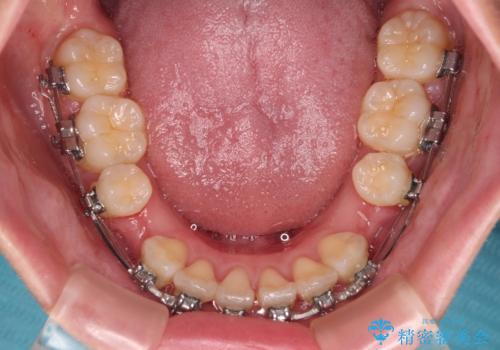

- 矯正装置

- メタルブラケット

- 1年10ヶ月

- 前歯がくちばしのように飛び出していることを気にして来院された患者様です。

唇が前方に突出している横顔が気になっているため、上下左右の第一小臼歯4本を抜歯し、ワイヤー装置にて矯正治療を行うこととしました。